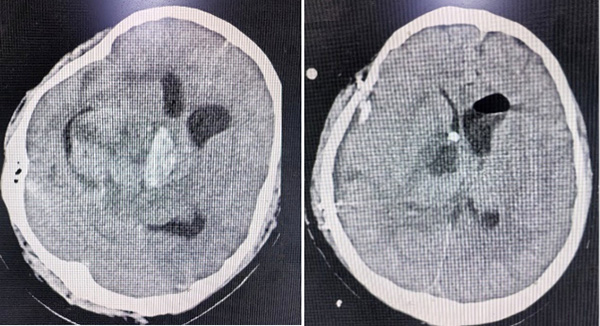

两名患者情况类似,均为颅内巨大肿瘤伴肿瘤卒中,出现因脑干受压,瞳孔增大,如果没有迅速得到处理,患者一般会在几小时内陷入昏迷,造成死亡。面对这种紧急情况,张玉琪教授接到值班医生汇报,没有丝毫犹豫,立即组织团队进行术前准备,并迅速投入到紧张的手术中,张玉琪教授以高超的医术和团队成员、麻醉科的鼎力配合,成功为两名患者完成了急诊手术,最终两名患者均转危为安。

患者1 手术前后脑部CT影像